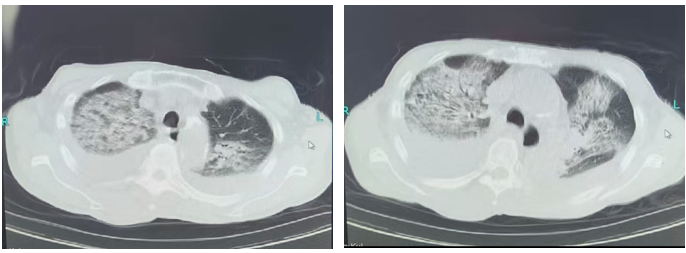

北京中医医院急诊为吴爷爷完善胸部CT后确认:双肺大面积渗出、实变,即俗称的“白肺”,同时双侧胸腔积液明显。老人神志尚清,但精神萎靡,呼吸急促,血氧下降,病情危重。

经过近两周的综合救治,吴爷爷的变化令人欣喜。复查胸部CT显示:双肺弥漫性渗出、实变已明显吸收,“白肺”基本消退。临床症状上,他不再喘憋,咳血消失,血氧恢复正常。